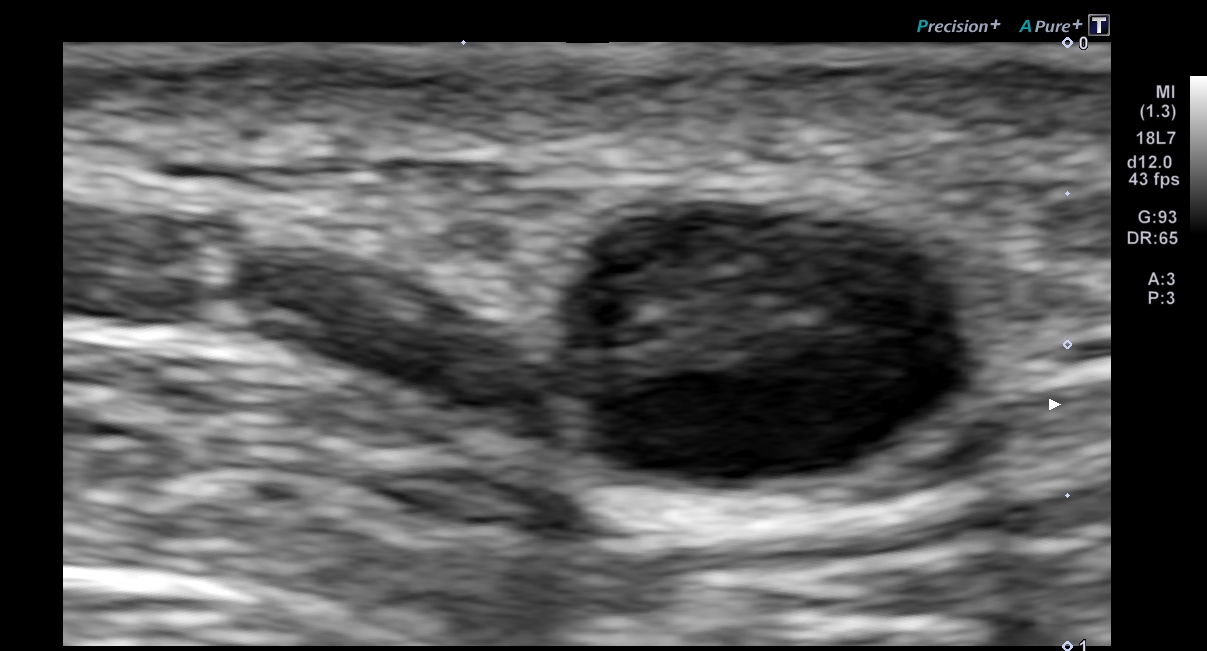

超音波(エコー)

下記など多くの診断ができます。

各項目をクリックすると診断画像が表示されます

超音波(エコー) 診断画像

- 粉瘤

- 頸部リンパ節転移